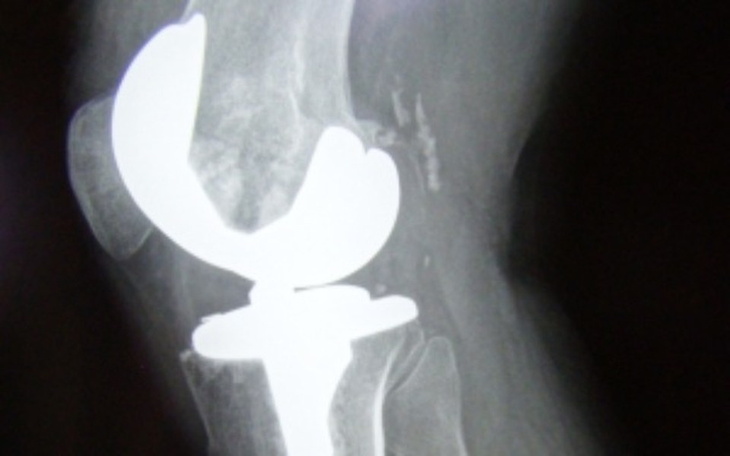

Witajcie mam na imię grzegorz od urodzenia walcZe z wyrodnieniem stawem kolanowym bardzo proszę o pomoc czekam na zabieg ale nie mam całości pieniędzy na pokrycie operacji oraz rechabilitacji każdy grosz sie liczy